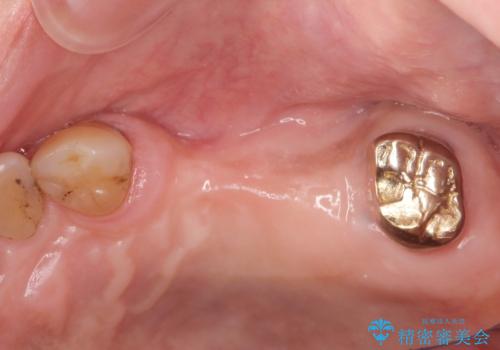

- 奥歯を失い半年間入れ歯を使用してみたが、とにかく咬めない、食事を楽しむことができない!と

咬合機能の回復を求めて来院されました。

しっかりとまた物を噛めるようになるために、インプラントを用いて咬合機能を回復していきます。